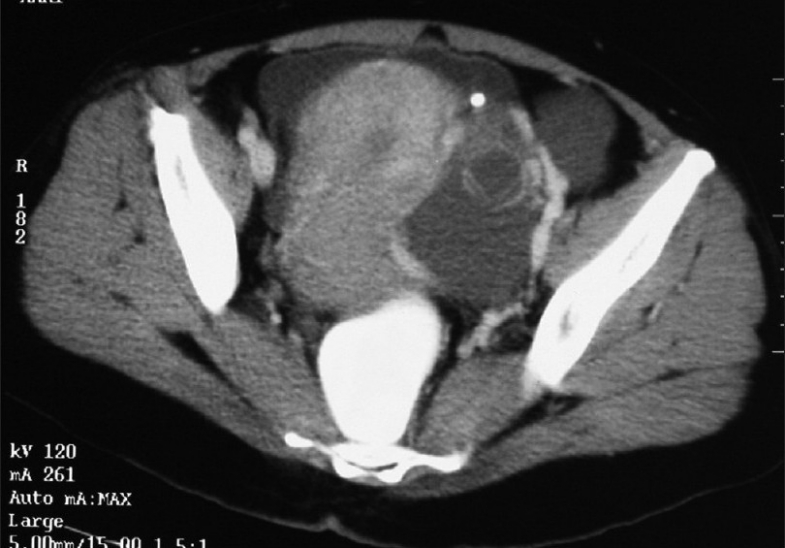

Patient was evaluated with routine blood investigations, tumor markers and imaging, including ultrasound and a CT scan of the abdomen and pelvis[Figure 1]. The investigation reports are summarized in Table 1.

| Figure 2 Contrast-enhanced CT scan showing tumor with increased vascularity in the periphery

| CT abdomen and pelvis | A mixed-density lesion of 12 cm in the left adnexal region with enhancing solid and cystic components. Tortuous enlarged vessels noted in the periphery of the lesion. Moderate ascites. Right ovary normal. Left ovary not visualized separately. Uterus bulky with no focal lesions |

In this case, a color Doppler was not done; but the CT scan finding of tortuous enlarged vessels, noted in the periphery of the mass with ascites, and the markedly elevated CA-125 level were strongly suggestive of malignancy.